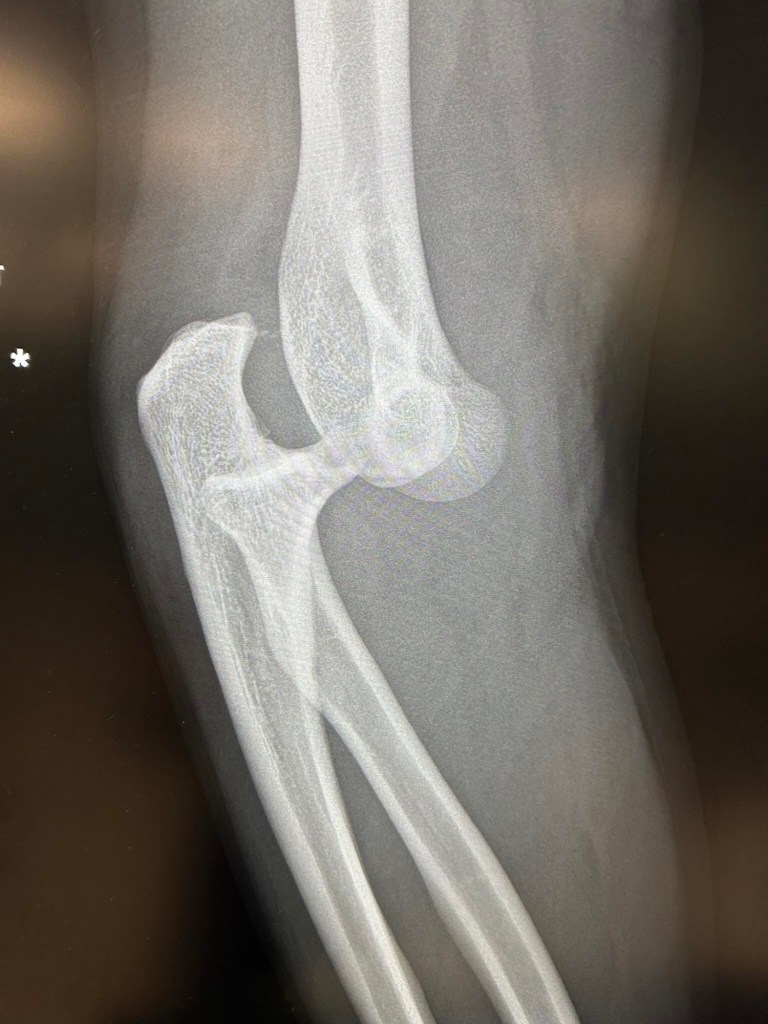

Look away now if you are squeamish :-//

Angus’s dislocated elbow !! The funniest thing is, when they knocked him out to put his elbow back in, (which was difficult because he is so big and muscly apparently !!!) he was talking about sandwiches, and telling the nurses not to put tomato on his sandwiches because he doesn’t like tomatoes lol